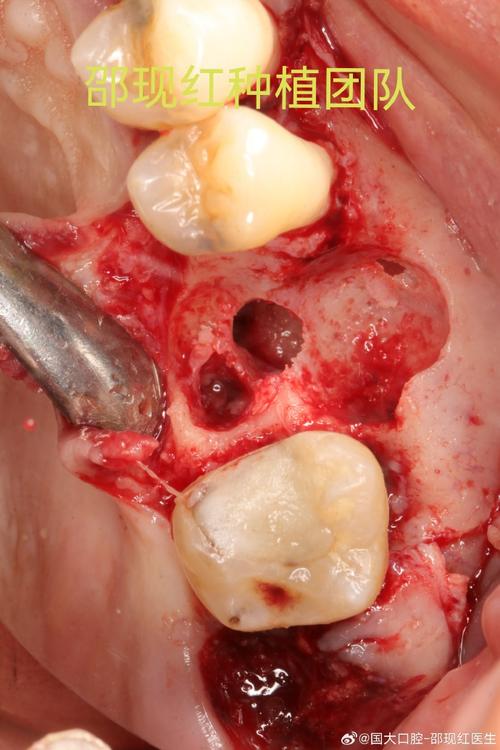

- 种植体周围清创术:翻瓣刮除种植体周围炎性肉芽组织,用生理盐水、双氧水反复冲洗术区,保留稳定种植体。

- 上颌窦开窗引流术:通过下鼻道或唇侧开窗,引流窦腔内脓液,同时处理窦黏膜病变。

- 种植体取出+窦腔修补:若种植体松动、严重污染或骨质破坏广泛,需取出种植体,彻底清创窦腔,使用骨粉、胶原膜等材料修补穿孔,待3-6个月骨愈合后二期种植。